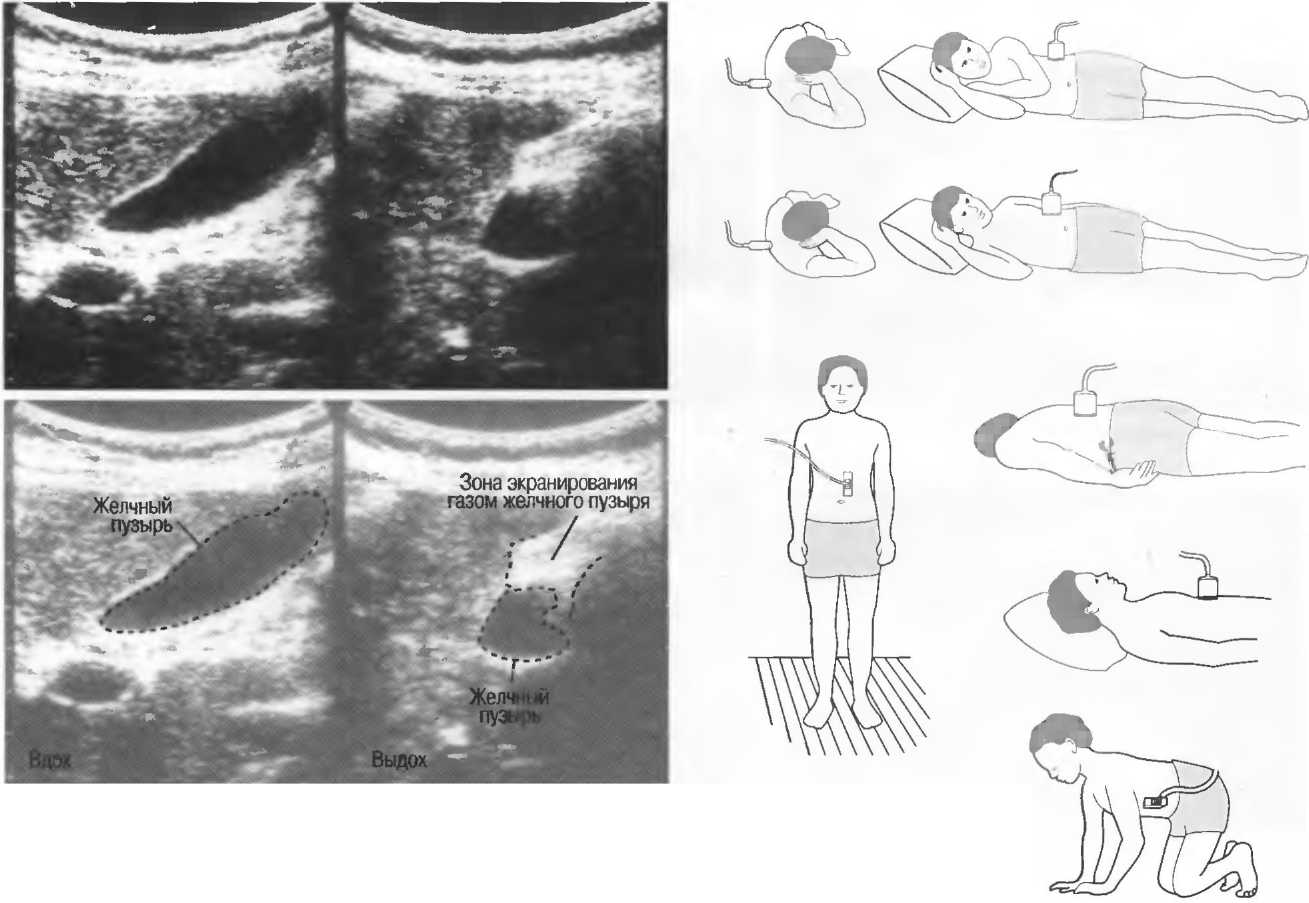

Газ отражает ультразвук и экранирует ткани, расположенные сзади, в результате преломления и акустической тени от газа. Газ в кишечнике может экранировать печень, поджелудочную железу, парааортальные лимфоузлы, матку, яичники. Иногда удается сместить газ в кишечнике, например при наличии наполнения мочевого пузыря матка и яичники почти всегда легко визуализируются, так как кишечные петли «убраны» из поля зрения. В других случаях бывает необходимо делать косые, латеральные или дорсальные сканы в положении пациента стоя или сидя (рис. 19).

Рис. 19. На эхограмме, полученной во время вдоха (слева), желчный пузырь визуализируется целиком, во время выдоха (справа) более чем половина желчного пузыря экранирована кишечным газом. |

Возможные положения пациента при экранировании тканей кишечным газом |